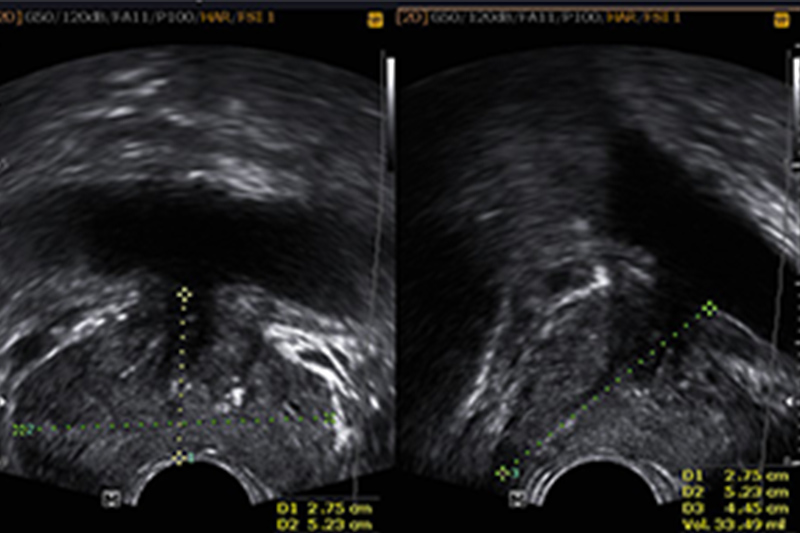

전립선 비대증은 남성에게 흔히 나타나는 질환으로, 나이가 들면서 전립선이 점점 커지는 현상을 의미합니다. 주로 50대 이상에서 발생률이 높아지며, 요도를 압박하여 다양한 배뇨 문제를 일으킬 수 있습니다.

- 정기적인 건강검진: 특히 50세 이상 남성은 연 1회 정기검진으로 전립선 건강을 체크해야 합니다.